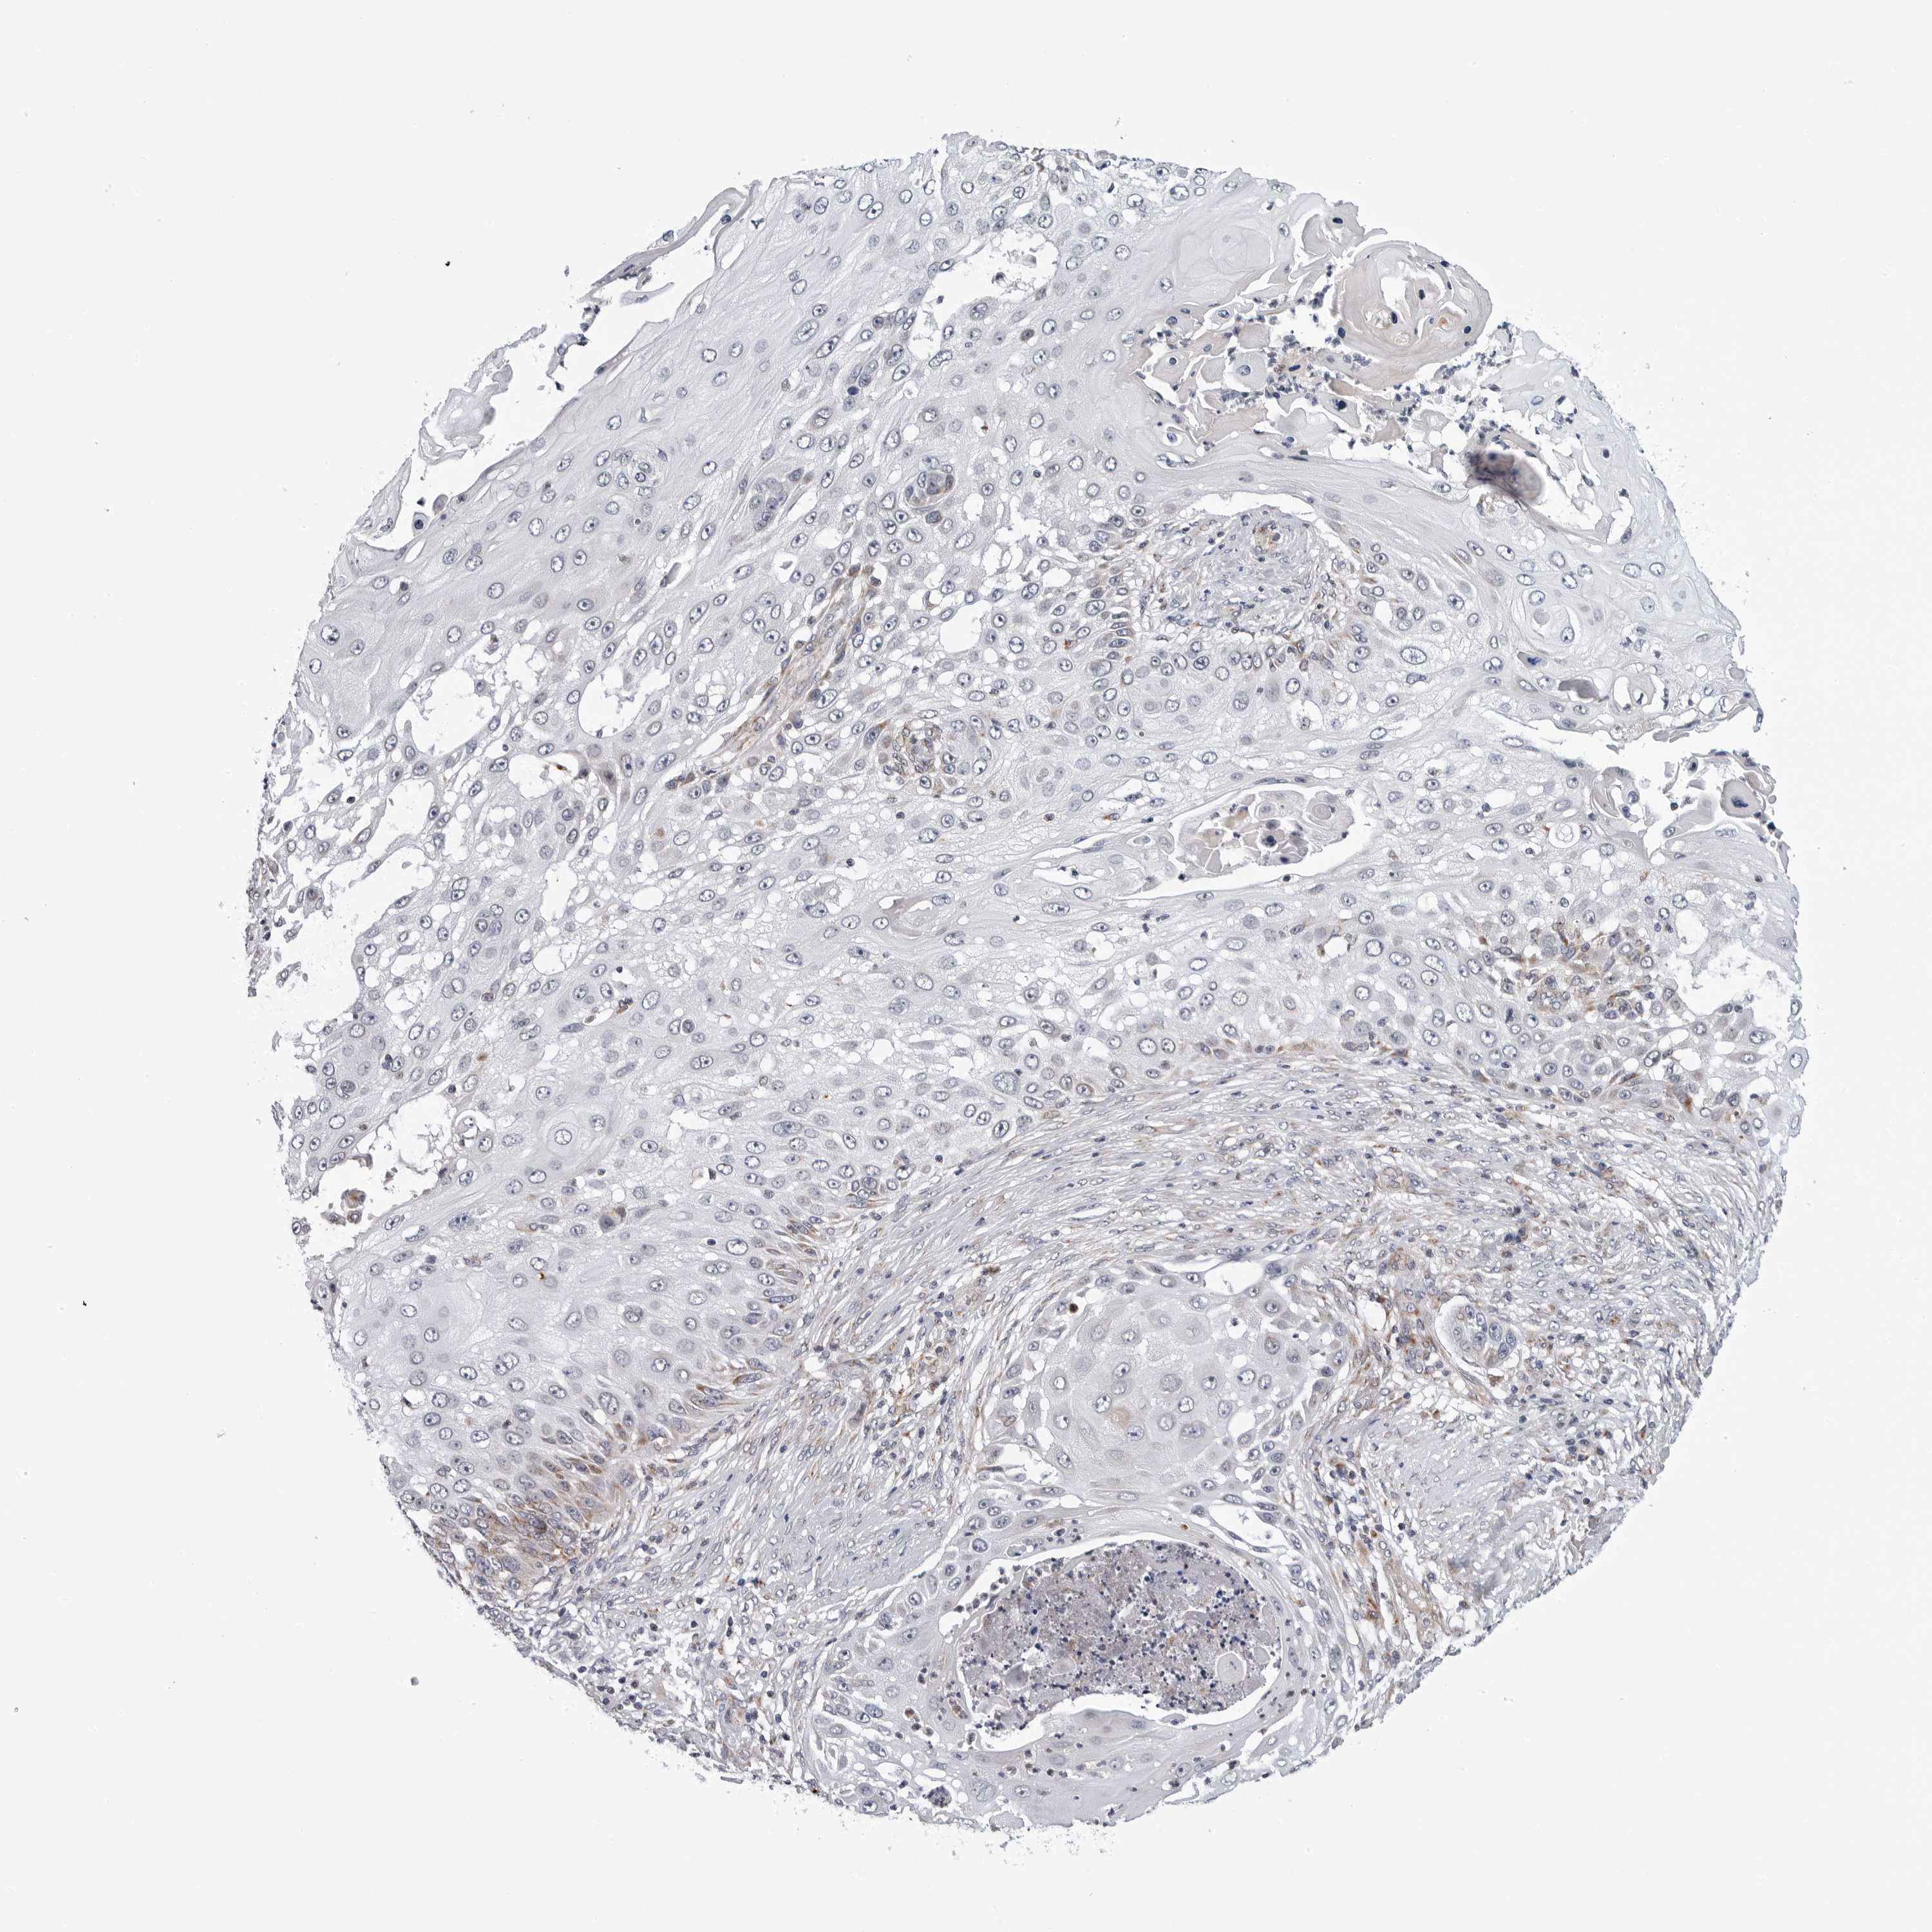

SKIN CANCER - Protein expressioni

A mouse-over function shows sample information and annotation data. Click on an image to view it in a full screen mode. Samples can be filtered based on level of antibody staining by selecting one or several of the following categories: high, medium, low and not detected. The assay and annotation is described here.

Each image is clickable and will lead to virtual microscopy that enables deeper exploration of all samples and also displays staining intensity scores, fraction scores and subcellular localization as well as patient and tissue information for each sample.

Antibody HPA027379

Squamous cell carcinoma, metastatic, NOS